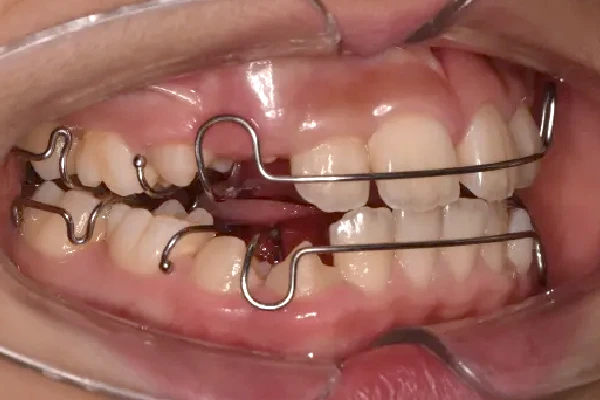

反対咬合

| 診断名・主訴 | 前歯反対咬合 |

|---|---|

| 年齢・性別 | 12歳・男性 |

| 治療期間・回数 | 1年半 18回 |

| 治療に用いた主な装置 | リンガルアーチ(前方誘導弾線) |

| 抜歯部位 | なし |

| 治療費 | 35万円(税抜) |

| リスク・副作用 | 装置による違和感・疼痛・歯肉退縮・歯根吸収・虫歯のリスクなど |

治療中